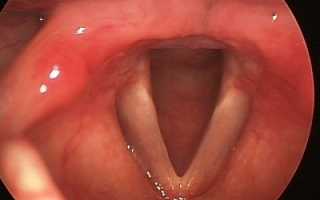

Пациент 11 лет, был направлен на прием к лору с жалобами на затрудненное дыхание, сухость в горле и осиплость голоса. При осмотре: общее состояние ребенка не нарушено, слизистая гортани гиперемирована, отечна, голосовые складки розовые, смыкаются не полностью. Диагноз: катаральный острый ларингит.

Назначено лечение: голосовой покой, диета, гортанные заливки с масляным раствором витамина Е, щелочные ингаляции и Эфизол (пастилки для рассасывания).

Через неделю состояние ребенка нормализовалось и он вернулся к привычному образу жизни.